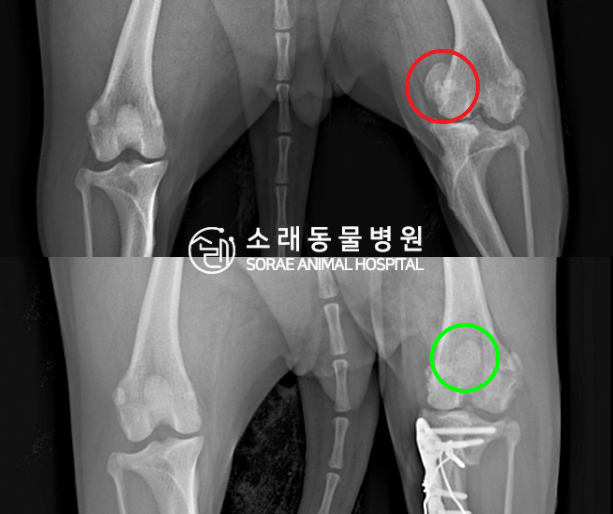

수술전과 수술후에 촬영한 한이의 슬개골

방사선 사진입니다. 나란히 놓고 비교해보니

슬개골의 위치에 확연한 차이가 있는 것을

확인해 볼 수 있는데요. 내측으로 탈구되어 있던

슬개골이 원래 제자리인 활차구에 예쁘게

자리 잡고 있는 모습을 확인할 수 있었습니다.